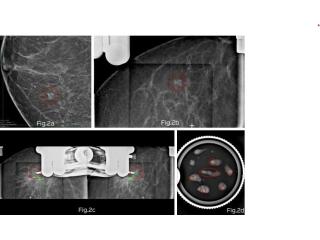

Picture This specializes in minimally invasive Stereotactic Vacuum Assisted Breast Biopsy in Mumbai, ensuring precise tissue sampling for early breast cancer detection. Our advanced imaging guidance allows accurate targeting of suspicious areas, reducing the need for surgical biopsies. Patients benefit from quicker recovery, minimal discomfort, and highly reliable results reviewed by experienced breast imaging experts. Patients across Mumbai trust us for our commitment to accuracy, safety, and compassionate care throughout the diagnostic journey. Early detection is key to better treatment outcomes—choose Picture This for safe and precise Stereotactic Vacuum Assisted Breast Biopsy in Mumbai. Book your appointment today.